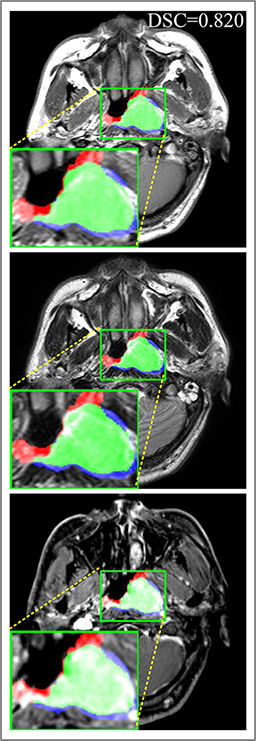

Refer to caption

Figure 10: Examples of 3D predicted results for different methods. (a) Ground truth. (b) Patch-based CNN (CET1). (c) Multi-modality patch-based CNN. (d) U-net (CET1). (e) 3D U-net (CET1). (f) Input-level fusion. (g) Merging encoders’ features. (h) MMFNet + multi-MLP + stdPool + self-transfer.

Comparison with related works. Table 1 reports the values of meanDSC𝑚𝑒𝑎𝑛𝐷𝑆𝐶meanDSC, meanASD𝑚𝑒𝑎𝑛𝐴𝑆𝐷meanASD and meanHD𝑚𝑒𝑎𝑛𝐻𝐷meanHD for different methods. Predicted masks of different methods are illustrated in Figure 9 and Figure 10, which respectively present results in 2D and 3D images. Through comprehensively analyzing these results, the proposed MMFNet actually have the following properties:

(i) It directly fuses 3D MRI images rather than 2D slices. Thus, it can effectively use meaningful information from neighboring slices of MRI to realize NPC segmentation. As shown in Table 2, MMFNet can bring 12.26%percent12.2612.26\%, 8.52mm8.52𝑚𝑚8.52mm and 81.19mm81.19𝑚𝑚81.19mm improvements in meanDSC,meanASD𝑚𝑒𝑎𝑛𝐷𝑆𝐶𝑚𝑒𝑎𝑛𝐴𝑆𝐷meanDSC,meanASD and meanHD𝑚𝑒𝑎𝑛𝐻𝐷meanHD compared to the best method based on 2D images (Multi-modality patch-based CNN). And Figure 10 shows that 3D-based methods have less isolated regions (false positives) than 2D-based ones.

(ii) It segments NPC by fusing multi-modality MRIs with the multi-encoder network. Thus, it can learn complementary and interdependent features from different modalities of MRI for final decisions. Additionally, comparing with input-level fusion networks and decision-level fusion networks, layer-level fusion networks (including MMFNet) can effectively capture informative features from different modalities of MRI and fuse low-level features and high-level features.

(iii) It uses a fusion block to fuse low-level features from different modalities of MRI and prepare these low-level features for the fusion with high-level features. Thus, it can more effectively fuse information from various sources. It also uses the self-transfer strategy to initialize the netwerk. Hereby, it can stimulate encoders to make full mining of meaningful features from modality-specific MRI. And it finally improve base multi-encoder-based network (Merging encoders’ fetures) by 2.64%percent2.642.64\%, 1.10mm1.10𝑚𝑚1.10mm and 11.88mm11.88𝑚𝑚11.88mm in meanDSC,meanASD𝑚𝑒𝑎𝑛𝐷𝑆𝐶𝑚𝑒𝑎𝑛𝐴𝑆𝐷meanDSC,meanASD and meanHD𝑚𝑒𝑎𝑛𝐻𝐷meanHD.